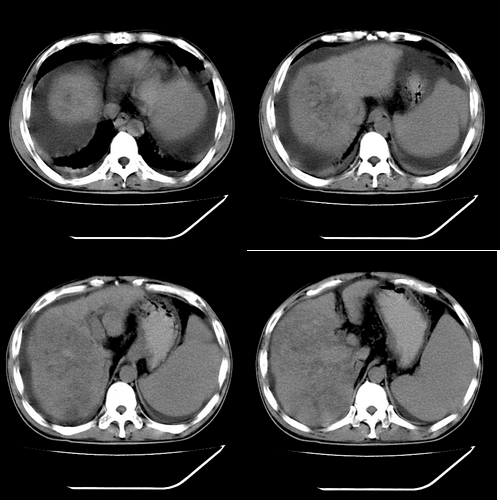

以下是引用yz在2006-6-2 12:20:00的发言:[br]肝左右叶比例失调,左叶体积明显缩小,肝边缘凹凸不平呈波浪状外观,肝左右叶可见不规则之斑片状低密度影,边界不清,以右叶为甚,肝门区增宽,增强后于动脉期病灶不均匀强化,门脉及延迟期均呈低密度,门脉主干及其右支无强化,以门脉右支明显,其内可见低密度影充填,门脉主干周围可见强化的细小侧支循环血管影。脾大,脾门血管明显增粗,脾后左侧膈脚前可见串珠状增粗强化血管影,并见胸腹水征。[br]1、考虑为弥漫性肝癌并肝门静脉主干及其右支癌栓形成,门脉海绵化。[br]2、肝硬化,脾大并门脉高压。[br]3、双侧少量胸水、腹水。